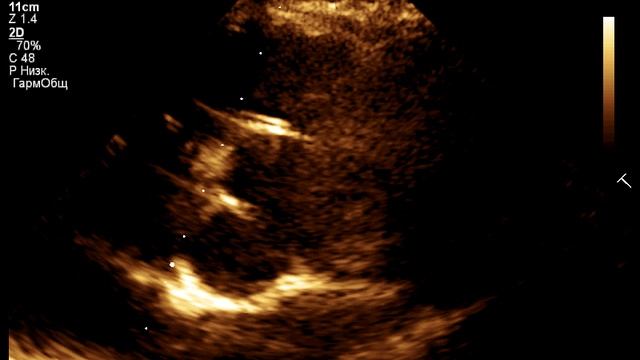

Видео

, видео от 2024-10-12 загрузил на rutube uzi_olga...